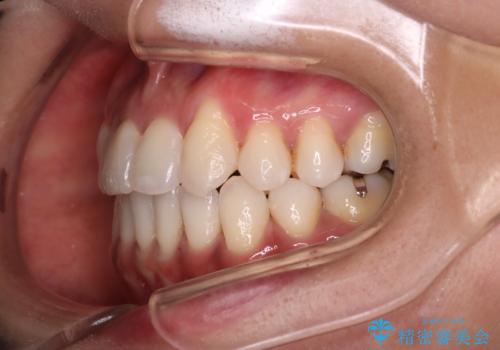

- 治療計画

抜歯矯正のため2年はかかってしまいましたが、きれいに並び患者様にも満足頂きました。